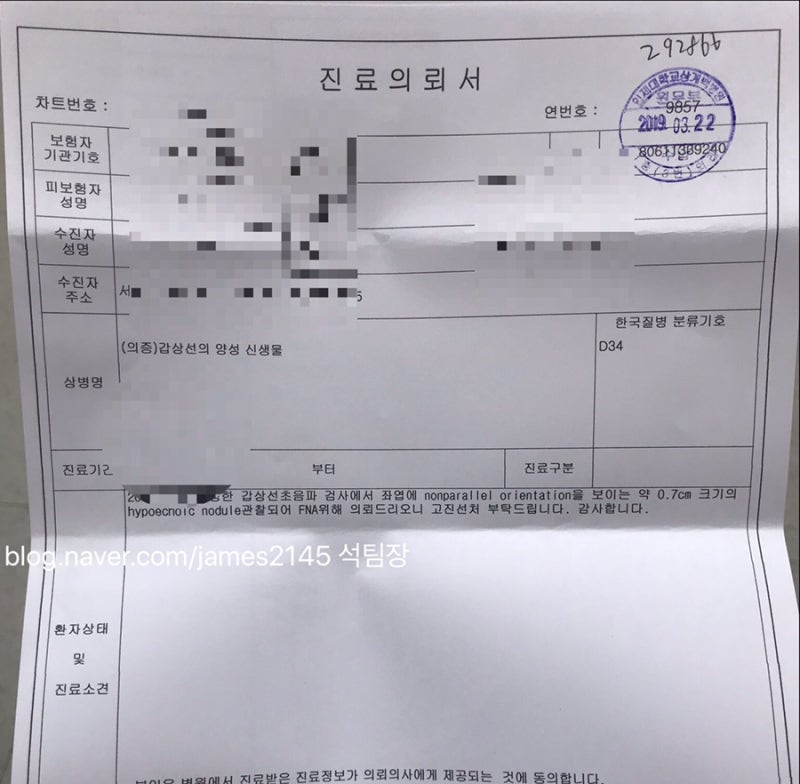

수치가 높게 나와서 정밀검사 진행했어요~

THS 정상 수치가 0.35~5.50인데,

29.6 나왔습니다.

군산에서 갑상선 기능 검사를 해야 하기 때문에

실비를 받기 때문에 서류

따로 챙겨달라고 했어요.

추가요금은 지불하지 않았고,

서류 잘 챙겨주셨어요.